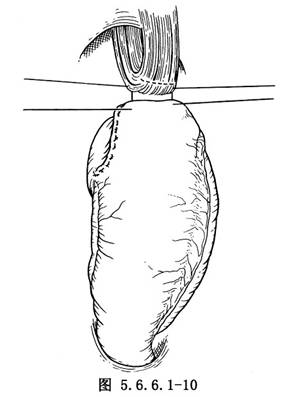

(3)游离胃:探查腹腔,如腹内无明显转移,在胃体上2/3与1/3交界处的小弯侧将胃肝韧带切开,再由相对应的胃大弯侧切开胃结肠韧带,用一条纱带越过胃后将胃向上牵引(图5.6.6.1-4)。继续切开胃结肠韧带,保留胃网膜右动脉,将韧带中的血管钳夹后切断结扎(图5.6.6.1-5)。切开胃脾韧带,切断结扎胃短动脉分支。在暴露术野时注意牵拉脾脏不能用力过大,以免撕裂脾脏(图5.6.6.1-6)。胃大弯侧游离足够以后,离断胃肝韧带,保留胃右动脉(图5.6.6.1-7)。在贲门下方附近的小弯侧摸到搏动的胃左动脉,用3把止血钳夹住,近侧两把,远侧1把,切断后先缝扎一道,再由其深部结扎一道(图5.6.6.1-8),缝扎胃侧血管断端。如此时胃左动脉近侧残端有出血,应先用指压住出血点,再请第一助手以拇指用力按压胸主动脉即可止血,用吸引器将积血迅速清除后,即可从容寻找到出血处予以处理。小弯侧游离完后,在离断贲门之前,请麻醉师将胃管连接在吸引器上持续吸引,将胃内容物尽量吸净,如此可以减少污染并方便吻合操作,吸引完后将胃管向外拔,使其尖端置于贲门上方3~4cm处。用大号直止血钳夹住贲门切断(图5.6.6.1-9)。胃侧断端用中号丝线贯穿缝合,再将浆肌层对拢间断缝合。食管侧断端用贯穿缝合封闭后用阴茎套保护之。将游离完毕的胃提至胸腔。